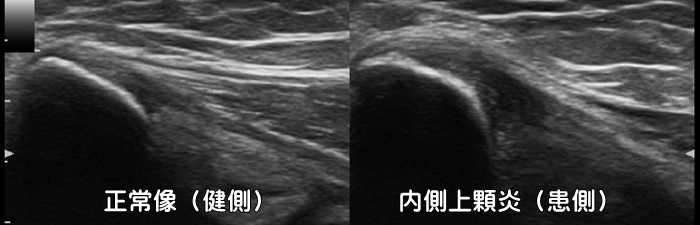

内側上顆炎・ゴルフ肘

肘の内側に痛みがあれば内側上顆炎(ゴルフ肘)が疑われます。エコーでは付着部の低エコー像が見られます。テニスのバックハンドでは外側上顆炎をフォアハンドでは内側上顆炎を発症します。